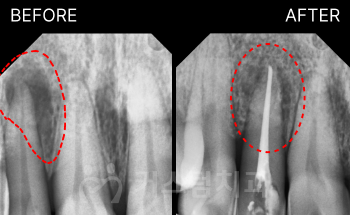

<어금니 임플란트 사례> "...